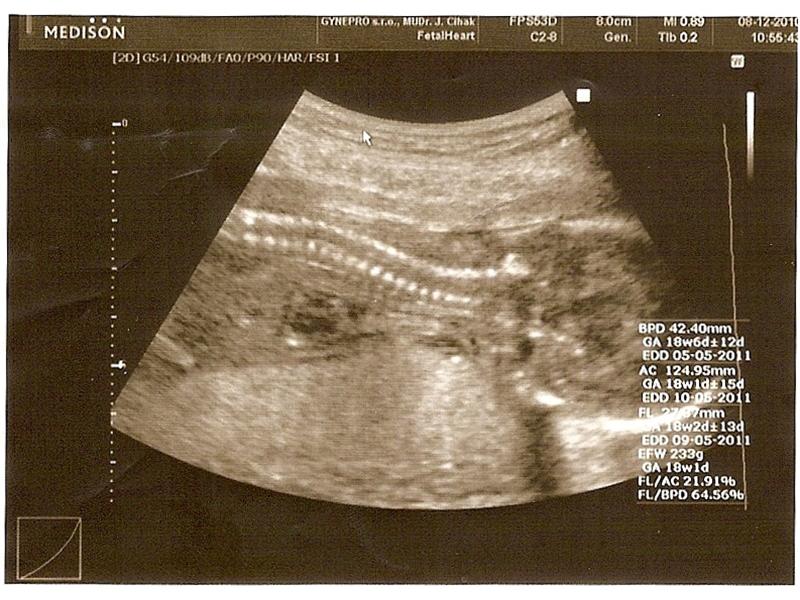

Zdroj: archiv redakce